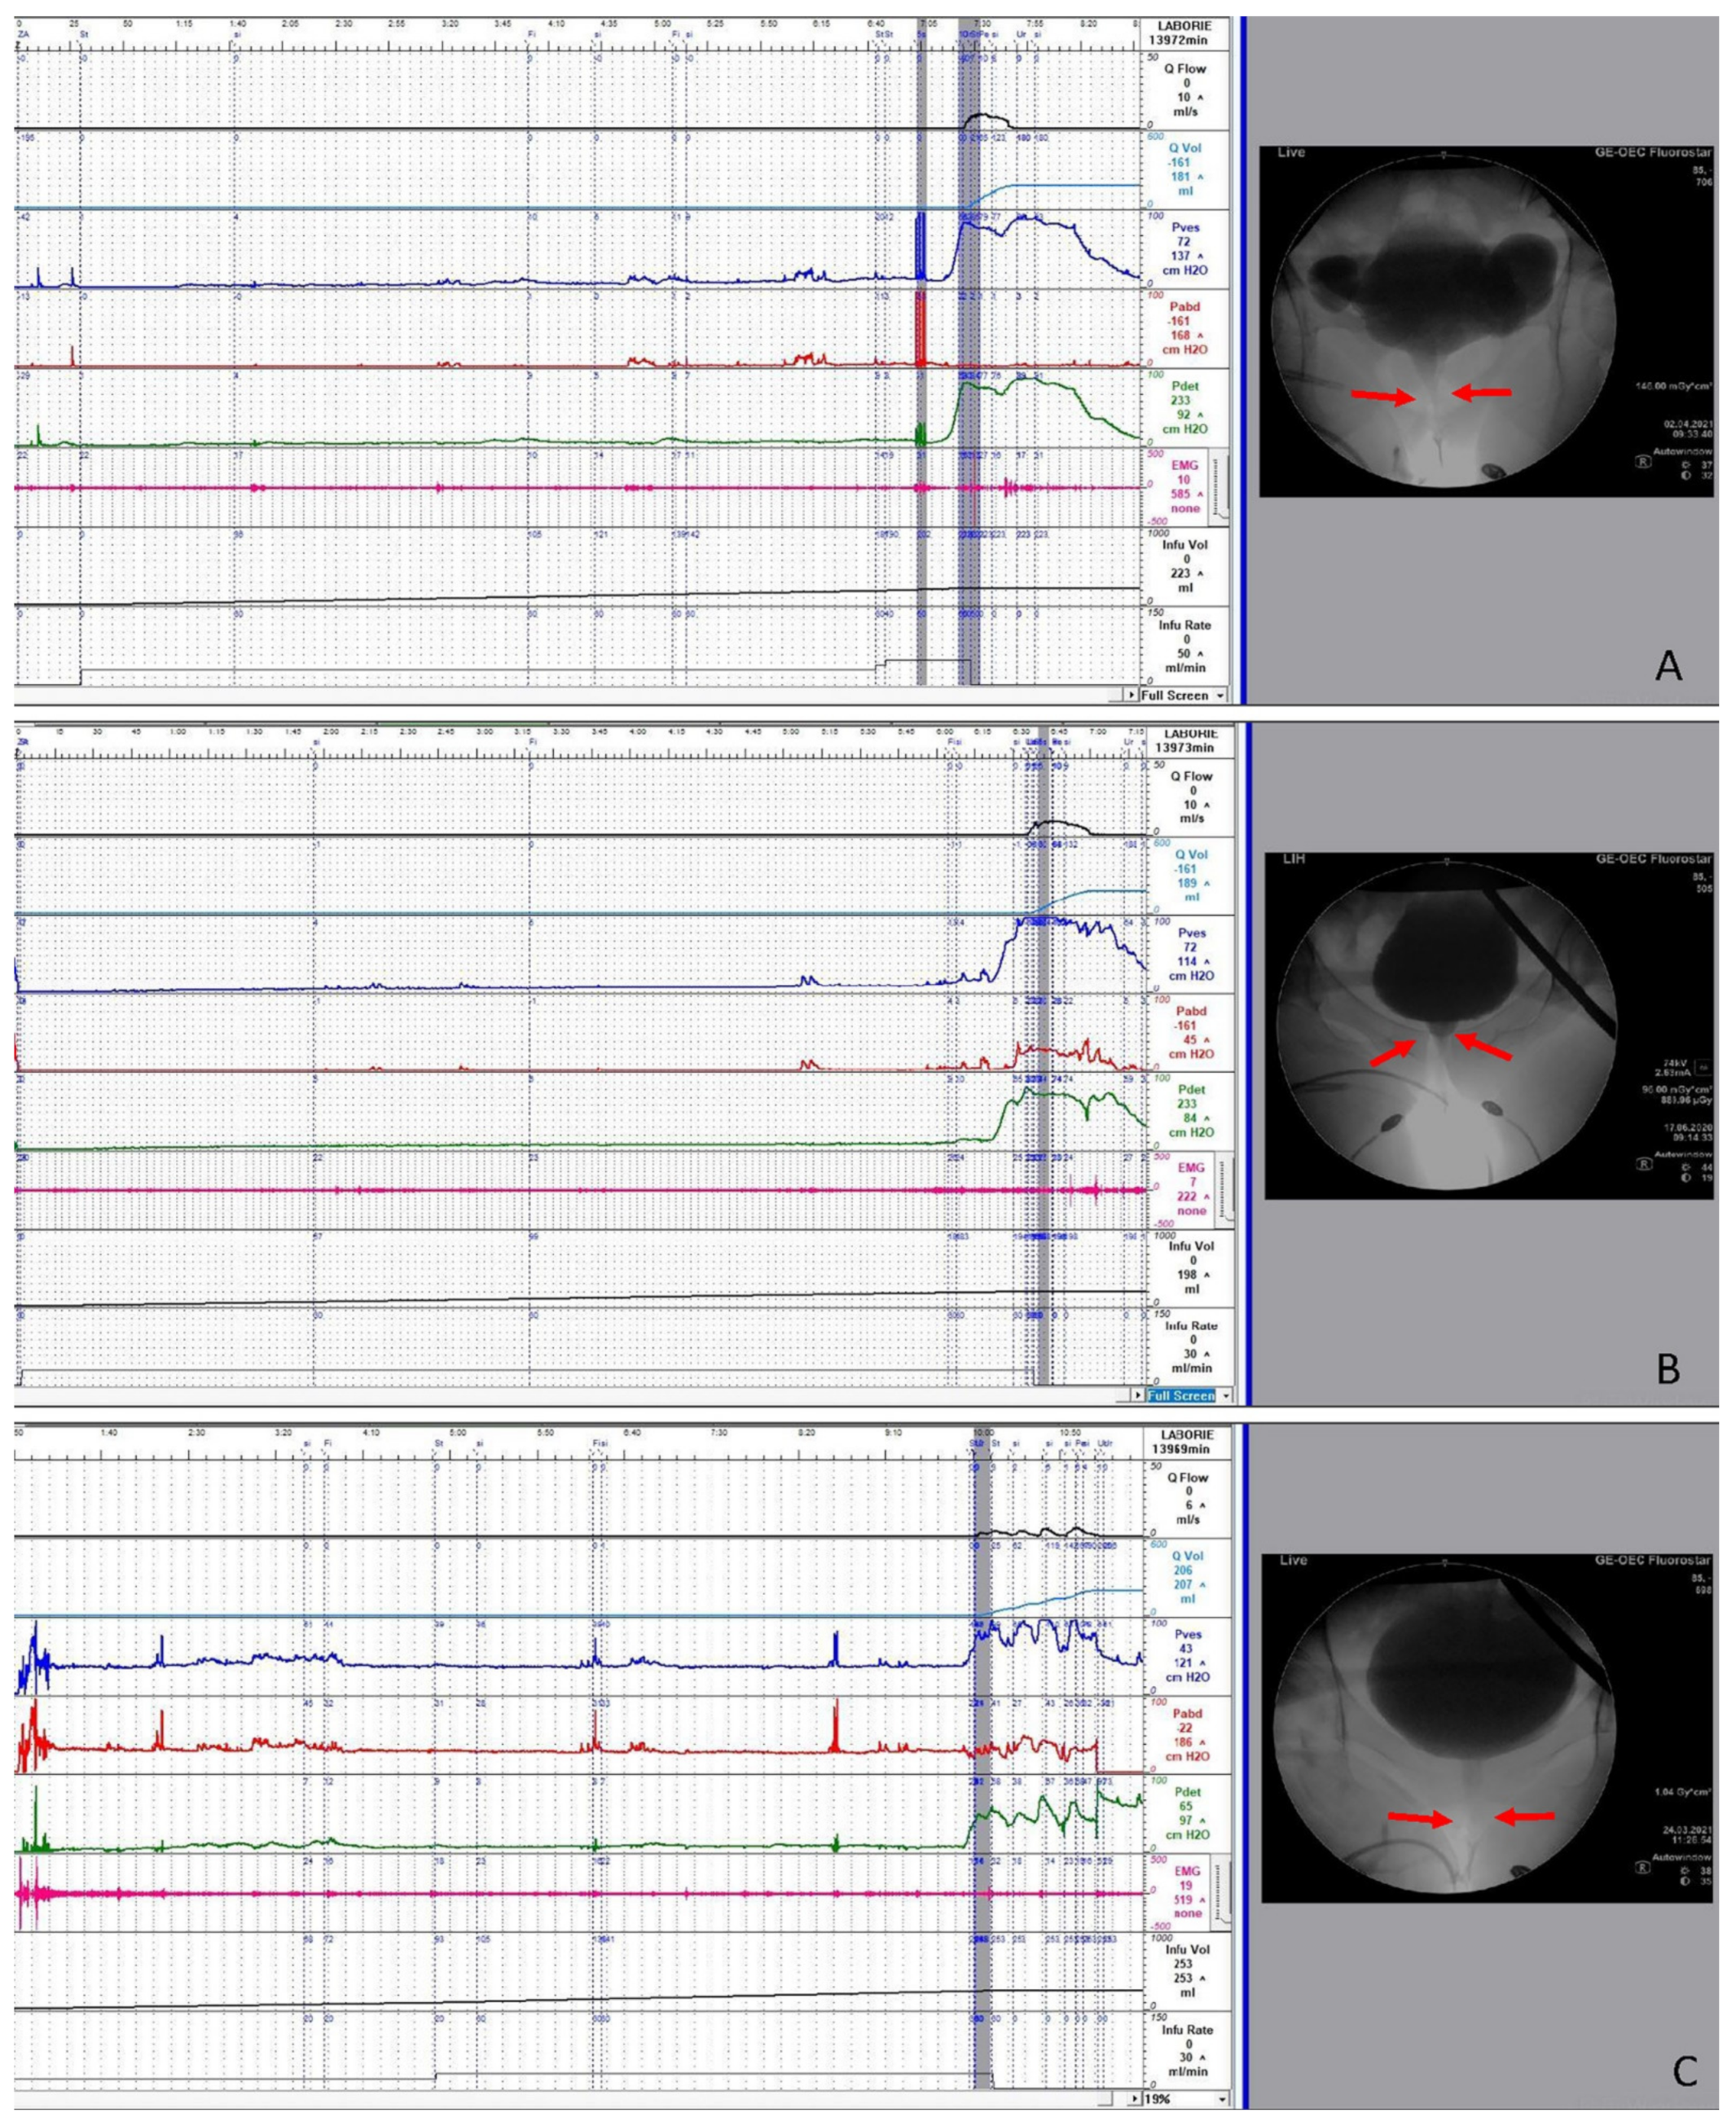

- Peng, C.H.; Chen, S.F.; Kuo, H.C. Videourodynamic analysis of the urethral sphincter overactivity and the poor relaxing pelvic floor muscles in women with voiding dysfunction. Neurourol. Urodyn. 2017, 36, 2169–2175. [Google Scholar] [CrossRef] [PubMed]